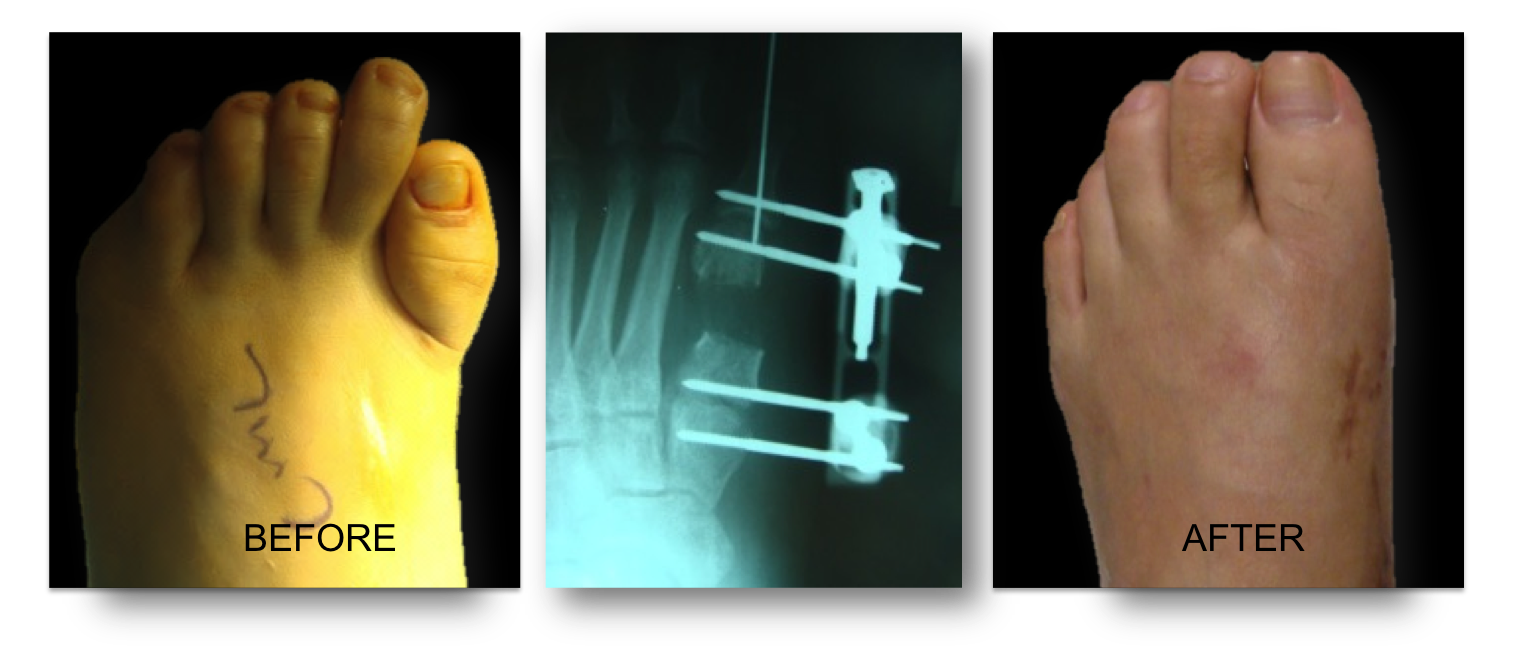

Below is a case of brachymetatarsia of the first metatarsal. Next to a short fouth toe and metatarsal this seems to be the most common type that we have seen. Xray in the middle shows the barely visible regenerate bone , look closely you can make out the bone shape.